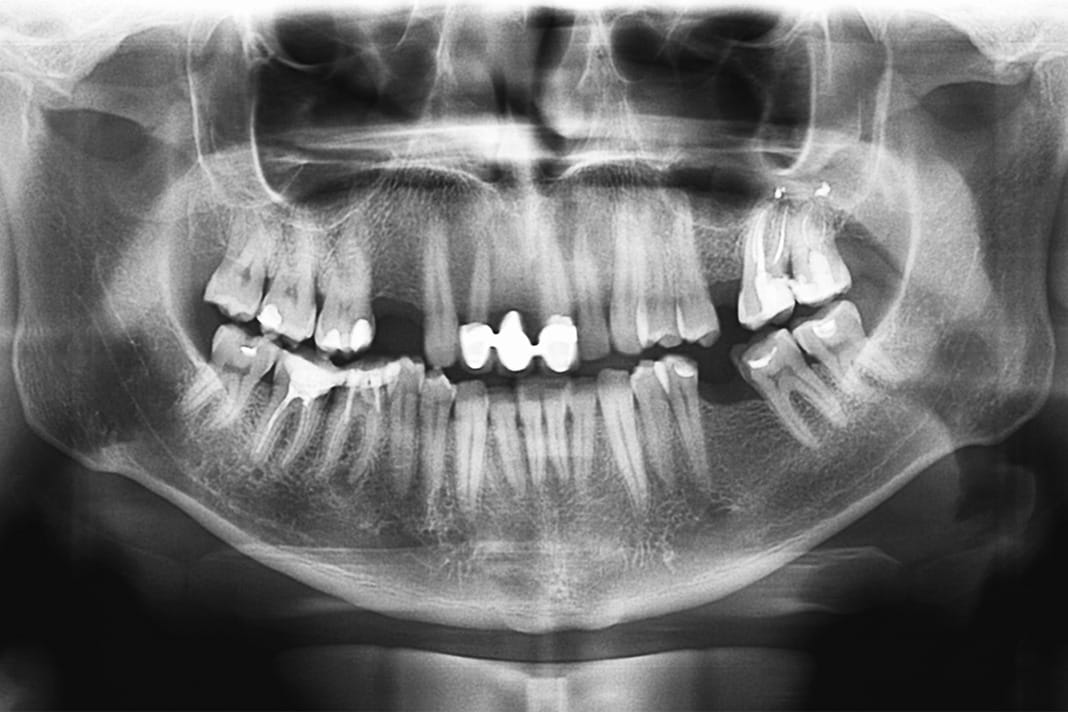

Bruxism is usually diagnosed during a dental examination, together with feedback from the patient. A differential diagnosis may be needed to distinguish bruxism from other disorders that affect bones and teeth, like movement disorders or bone tumors. Special instruments, like an electromyograph that records muscle movement, are helpful but are often hard to come by, unlike readily available panoramic radiograph equipment. Panoramic radiographs, which capture the entire mouth in one image, provide an easy view of potential jawline irregularities and are especially helpful for bruxism patients.

In this retrospective study, researchers compared panoramic radiographs of 100 bruxism patients, from the University of Basel’s Department of Oral Health and Medicine to a control group of 100 adolescents, from the Department of Pediatric Oral Health and Orthodontics. They chose adolescents for the control group since bruxism-related jawbone changes, they assumed, had not occurred yet due to their young age.

The Cranex D cephalometric radiograph system captured these radiographs between May 2010 and May 2017. Researchers selected radiographs that included the entire jawline and excluded images with blurs or markings, making them non-diagnostic. In order to focus on bruxism, they also excluded patients with other diagnoses, like bone disorders.

Paying special attention to the mandibular angle region and basal cortical bone, researchers looked for bone and jaw-shape changes that may result from extensive biting and clenching forces. They aimed to evaluate and grade these changes, which are common in bruxism patients, on a scale between 0 and 3.